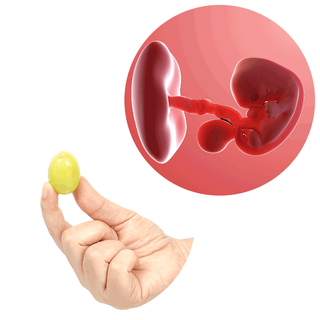

Kích thước và cân nặng của em bé

Bước vào tuần thứ 7 của thai kỳ, từ đầu đến chân của phôi thai có kích thước khoảng 10mm, nặng khoảng 0.8 gam và bằng quả nho.